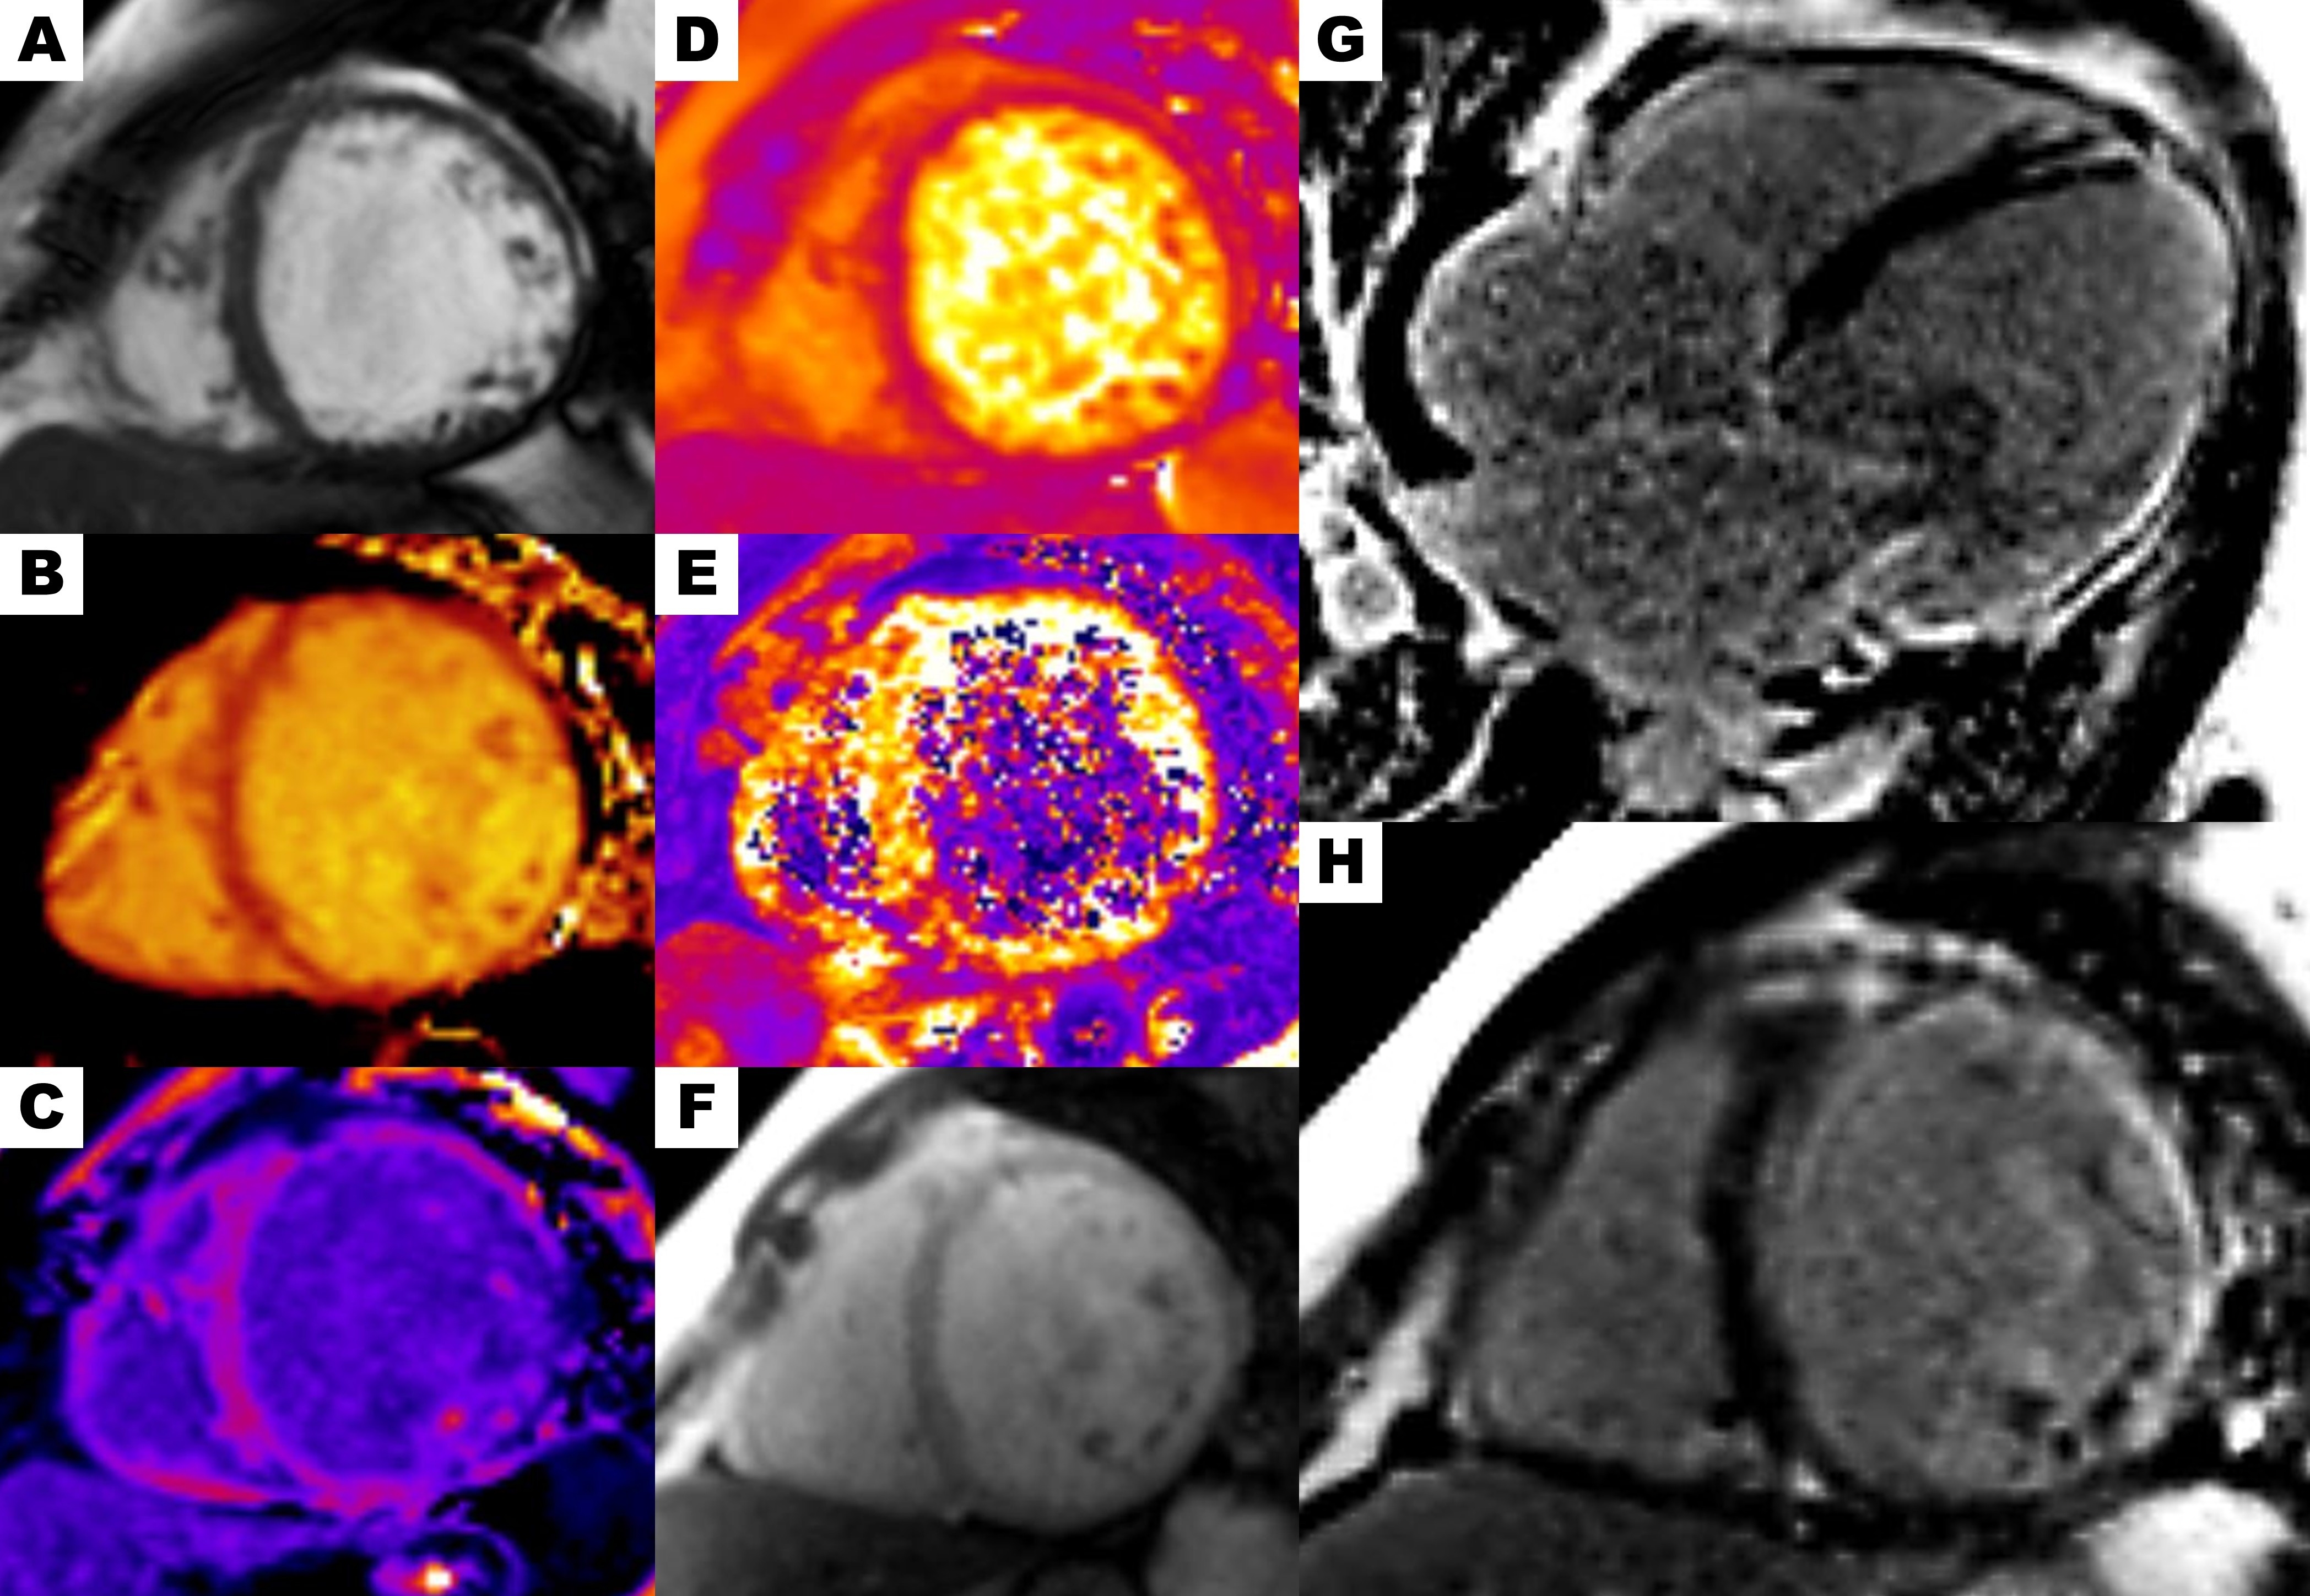

Diagnostic Techniques and Their Most Important Findings: Cardiac Magnetic Resonance (Fig 2-3):

- Transmural infarction in the right coronary and circumflex territories; subendocardial infarction in the left anterior descending territory.

- LGE burden: 57 g (46% of LV mass).

- Elevated T1 mapping values in the lateral wall across all three segments (1,124 ms) and increased extracellular volume (38%).

Figure 2. Cardiac magnetic resonance. (A) Balanced steady-state free precession cine short-axis view. (B) Elevated native T1 mapping values in the lateral wall across all three segments (1,124 ms). (C) Post-contrast T1 mapping showing an extracellular volume of 38%. (D) T2 mapping within the normal range. (E) T2* mapping within the normal range. (F) Short-axis first-pass perfusion demonstrating normal myocardial perfusion. Phase-sensitive inversion-recovery sequence showing LGE with transmural enhancement in the anterior, lateral, and inferior walls: (G) Four-chamber view, (H) Short-axis view.

Figure 2. Cardiac magnetic resonance. (A) Balanced steady-state free precession cine short-axis view. (B) Elevated native T1 mapping values in the lateral wall across all three segments (1,124 ms). (C) Post-contrast T1 mapping showing an extracellular volume of 38%. (D) T2 mapping within the normal range. (E) T2* mapping within the normal range. (F) Short-axis first-pass perfusion demonstrating normal myocardial perfusion. Phase-sensitive inversion-recovery sequence showing LGE with transmural enhancement in the anterior, lateral, and inferior walls: (G) Four-chamber view, (H) Short-axis view. Figure 3. Myocardial strain evaluation with feature tracking technique. (A–B) Circumferential strain. (C–D) Longitudinal strain.